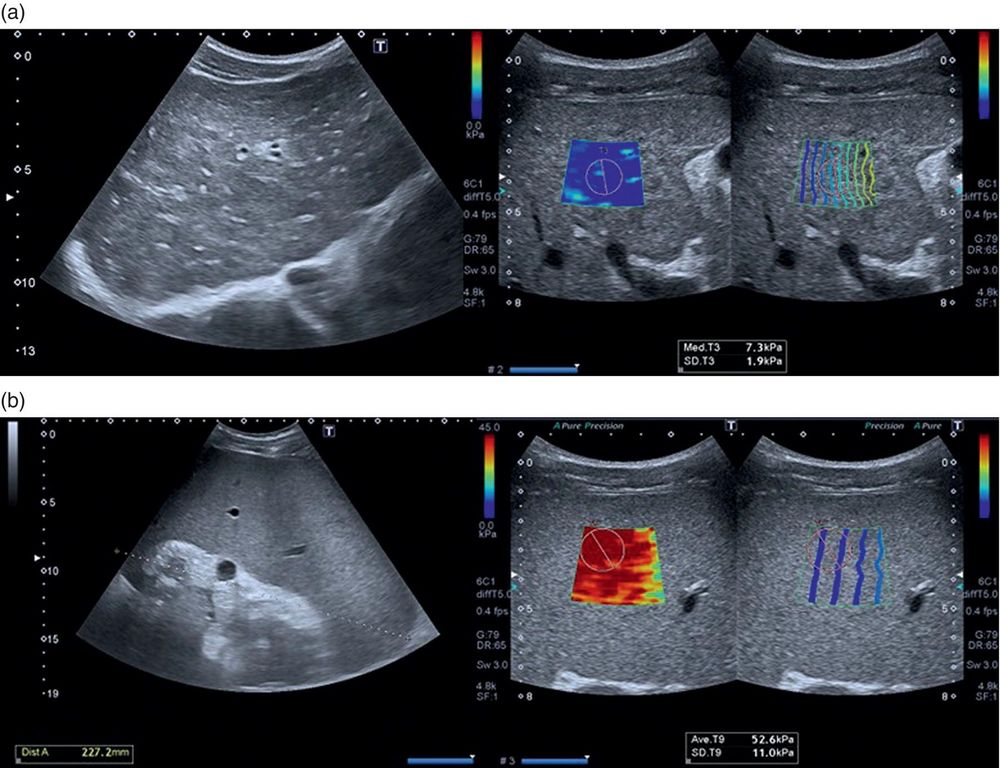

A rheumatic nodule can be visualized using both conventional (gray-scale) and elastography ultrasound. On a standard ultrasound image, the area appears relatively homogeneous, without clearly defined soft or fluid regions. However, when elastography is applied, softer areas (green, yellow, red) can be visualized, while the surrounding tissues appear stiffer (blue)

Principle: Under the same applied pressure, soft tissue deforms more, whereas hard tissue deforms less. This deformation is color-coded into an elasticity map.

There are two main types of elastography: Static elastography: tissue response to slow compression. Dynamic elastography: tissue response to rapid compression or vibration.

Another classification includes: Strain elastography (based on tissue deformation) and shear-wave elastography (based on shear wave propagation)

Strain elastography: provides quick, semi-quantitative tissue elasticity assessment. It is considered superior to B-mode and Doppler ultrasound for evaluating tendons and monitoring treatment response. Shear-wave elastography: provides more precise quantitative evaluation, overcoming depth limitations.

Shear-wave elastography